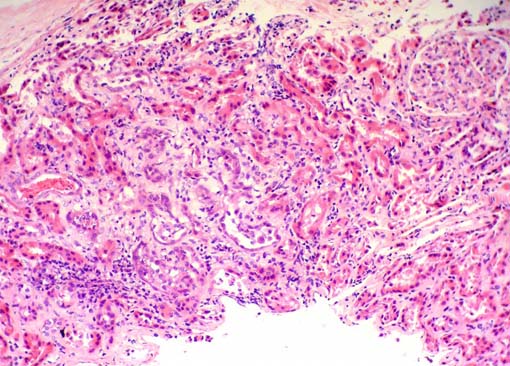

Observe las imágenes

de la biopsia renal.

Figura 1.

Algunos pequeños focos de inflamación tubulointersticial.

H&E, X100.